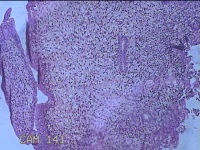

子宫腔赘生物

性别

女

年龄

33岁

临床诊断

子宫内膜息肉?子宫异常出血

一般病史

阴道流血12天。

标本名称

大体所见

灰白粉红色不规则肿物1.5x1.3x0.2cm一堆,表面糜烂。

图4